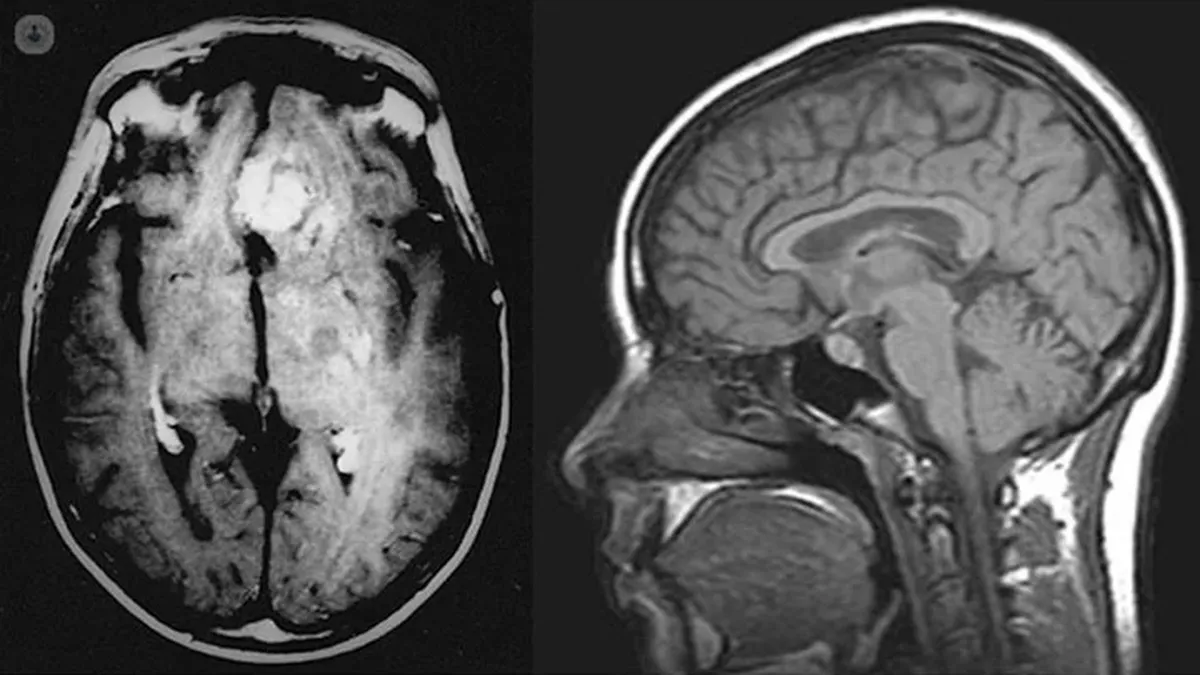

La situación para él cambiaría drásticamente en su última visita a un centro médico. Uno de los profesionales de la salud que allí se encontraba, perplejo por no tener idea alguna sobre lo que Oliver estaba experimentando, procedió a realizarle una prueba de escáner. Para su sorpresa, encontró algo.

El muchacho inglés llevaba consigo un tumor cerebral no diagnosticado. Quien lo atendió, la médica Shaveta Mehta, admitió que de no haber encontrado aquel tumor a tiempo, Oliver hubiese caído en coma 5 días después. “La detección de este tipo de alteraciones suelen ser un desafío”, remarcó.